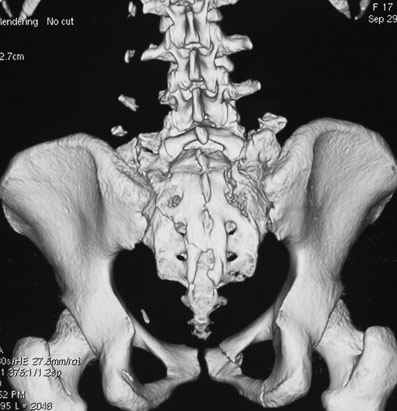

Травма 21.августа 2005г. На девочку в лесу упала береза. Доставлена в ближайшую ЦРБ. При поступлении установлен диагноз: Травматический шок 2-3 ст. Тупая травма живота. Забрюшинная гематома. Перелом костей таза с нарушением целостности тазового кольца. Перелом лонной и седалищной костей справа. Перелом поперечных отростков L3 - L5. Разрыв КПС справа. При поступлении выполнена диагностическая лапароскопия — выявлена обширная забрюшинная гематома. Было наложено скелетное вытяжение за бугристости обеих б/берцовых костей, больная уложена в гамак. Через неделю скелетное вытяжение демонтировано, гамак снят. Девочка уложена в положение «лягушки». Контрольные рентгенограммы через 4 недели после травмы. Заподозрен перелом дужки L5. Больная 26 сентября 2005 г. переведена в областную больницу в отделение детской ортопедии. При поступлении в локальном статусе: пальпация и перкуссия остистых и поперечных отростков L4-5 болезненная. Пальпация костей таза б/болезненная. С-м натяжения слабо положителен. Осевая нагрузка положительная. Движения в т/б суставах ограничены, болезненны. C-м прилипшей пятки отрицательный. C-м Ларрея и Варнейля отрицательный. Периферическая гемодинамика не нарушена.Неврологический статус: вторичная двусторонняя радикулопатия L5-S1. 29 сентября произведена компьютерная томография позвоночника и таза.

Судя по томограммам, радикулопатия может быть из-за компресии "конского хвоста" смещенным крестцовым позвонком, это хорошо видно на втором слева снимке. Если этот сегмент будет нестабилен и будет сохраняться неврологическая симптоматика, придется оперировать. Если неврологическая симптоматика уйдет и перелом стабилизируется, то можно обойтись без операции.